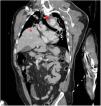

Varón de 49 años con traumatismo toracoabdominal cerrado tras colisión frontal por accidente de tráfico. En la body TAC se objetiva rotura de hemidiafragma derecho con herniación del lóbulo hepático derecho (asterisco) a la cavidad torácica, desplazamiento mediastínico y disección traumática de aorta descendente a la salida de la arteria subclavia izquierda (punta de flecha) en el plano coronal oblicuo (fig. 1) y transversal (fig. 2). Se realizó reducción quirúrgica urgente de la hernia diafragmática y aortografía diferida (fig. 3) con reparación aórtica mediante endoprótesis. La asociación de una rotura hemidiafragmática derecha y una disección aórtica traumáticas es muy inusual. Se asocia a mecanismos de alta energía-desaceleración, son potencialmente mortales y muertes evitables con un diagnóstico y tratamiento precoz.